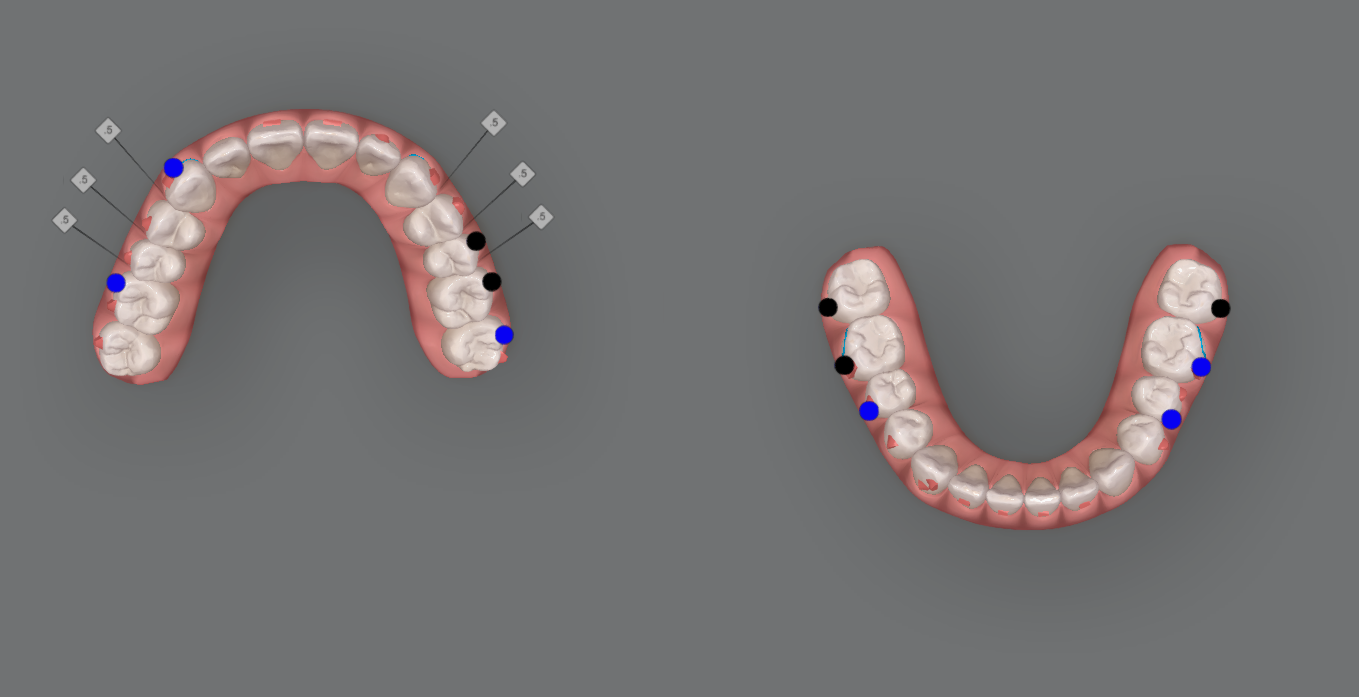

Kết quả đạt được

- Hai cung hàm được sắp xếp và phối hợp

- Cải thiện hình dạng cung hàm

- Đạt được sự hài hòa giữa hai cung hàm